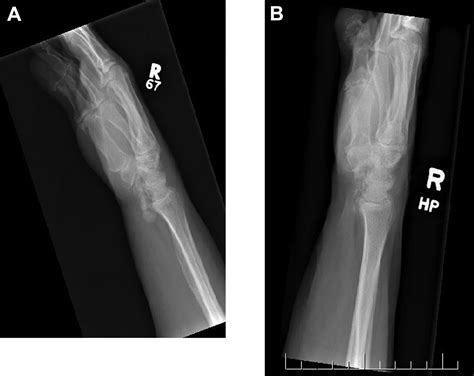

HADD can affect various joints, including the shoulder, elbow, wrist, hip, knee, and ankle. It can also occur in soft tissues such as tendons and ligaments. The most commonly affected areas are the shoulder and the wrist.

Diagnosing HADD involves a combination of clinical evaluation, imaging studies, and laboratory tests. The diagnostic process typically includes the following steps:

• Imaging Studies: X-rays, ultrasound, and magnetic resonance imaging (MRI) can help identify the presence of hydroxyapatite crystals and assess the extent of the deposits.

Imaging studies are particularly important in diagnosing HADD. X-rays can show calcifications in the affected areas, while ultrasound and MRI provide more detailed images of the soft tissues and joints. Laboratory tests can help rule out other conditions that may cause similar symptoms.